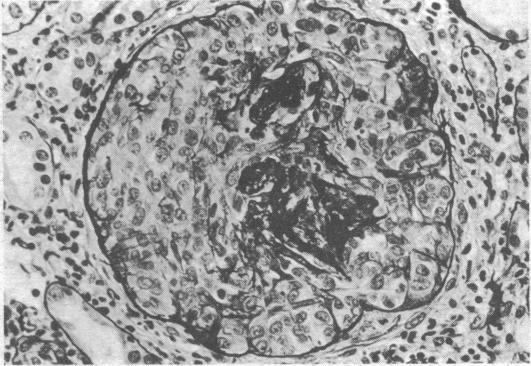

Eighty-four patients presented with acute renal failure and features suggesting a diagnosis of intrinsic renal disease other than "acute reversible renal failure." Renal biopsy proved valuable in establishing the diagnosis, in indicating the reversibility of the lesion, and in helping to decide on treatment.

84例患者表现为急性肾衰竭,且具有提示“急性可逆性肾衰竭”以外的原发性肾脏疾病诊断的特征。肾活检在确立诊断、提示病变的可逆性以及帮助决定治疗方案方面被证明是有价值的。